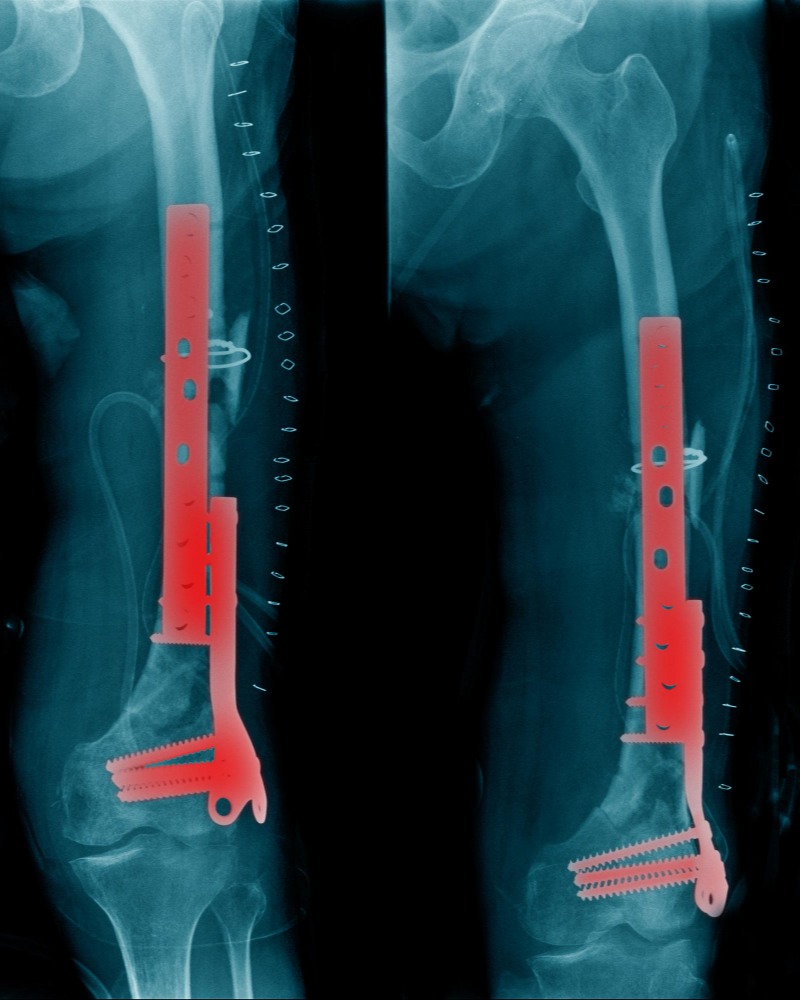

Pathological Fractures and Treatment in Mumbai